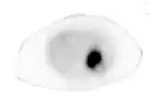

Wenn die Bestimmung der Plasma-Metanephrine wiederholt ein positives Ergebnis bringt, muss eine weiterführende Lokalisationsdiagnostik durchgeführt werden. Dies geschieht mittels bildgebender Verfahren wie Computertomographie und Sonographie oder MRT-Bildgebung. Bei der CT ist zu berücksichtigen, dass beim Einlaufen von Jod-Kontrastmittel Katecholamine ausgeschüttet werden können, was bei der MRT nicht der Fall ist. Die nuklearmedizinische Methode der MIBG-Szintigrafie (Metaiodobenzylguanidin) dient vor allem dem Ausschluss von Phäochromozytomen außerhalb der Nebenniere. Diese Substanz lagert sich vornehmlich in den betroffenen chromaffinen Zellen des Phäochromozytoms ab. Die neueste und zuverlässigste Form der nuklearmedizinischen Methode ist bei Phäochromzytomen das so genannte DOPA-PET. Es wird zurzeit (Stand 2012) in Deutschland allerdings lediglich in wenigen Zentren angeboten. Zusätzlich muss auf alle Fälle nach Tumoren eines eventuellen MEN-Syndroms gesucht werden.